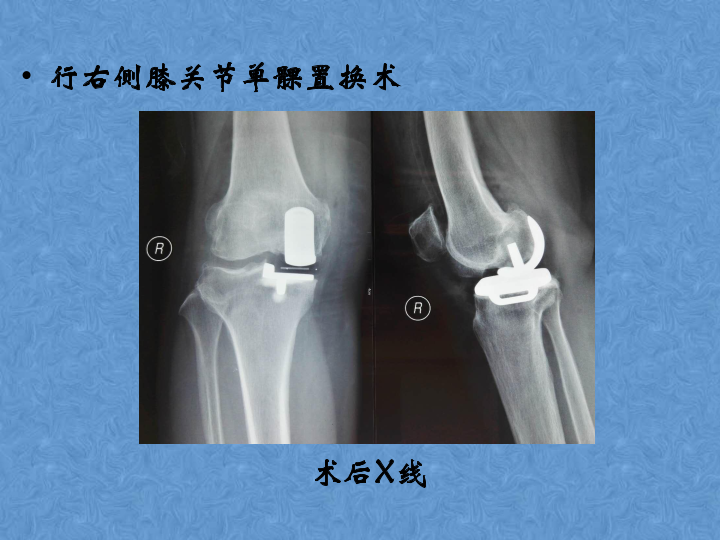

骨关节炎的阶梯治疗